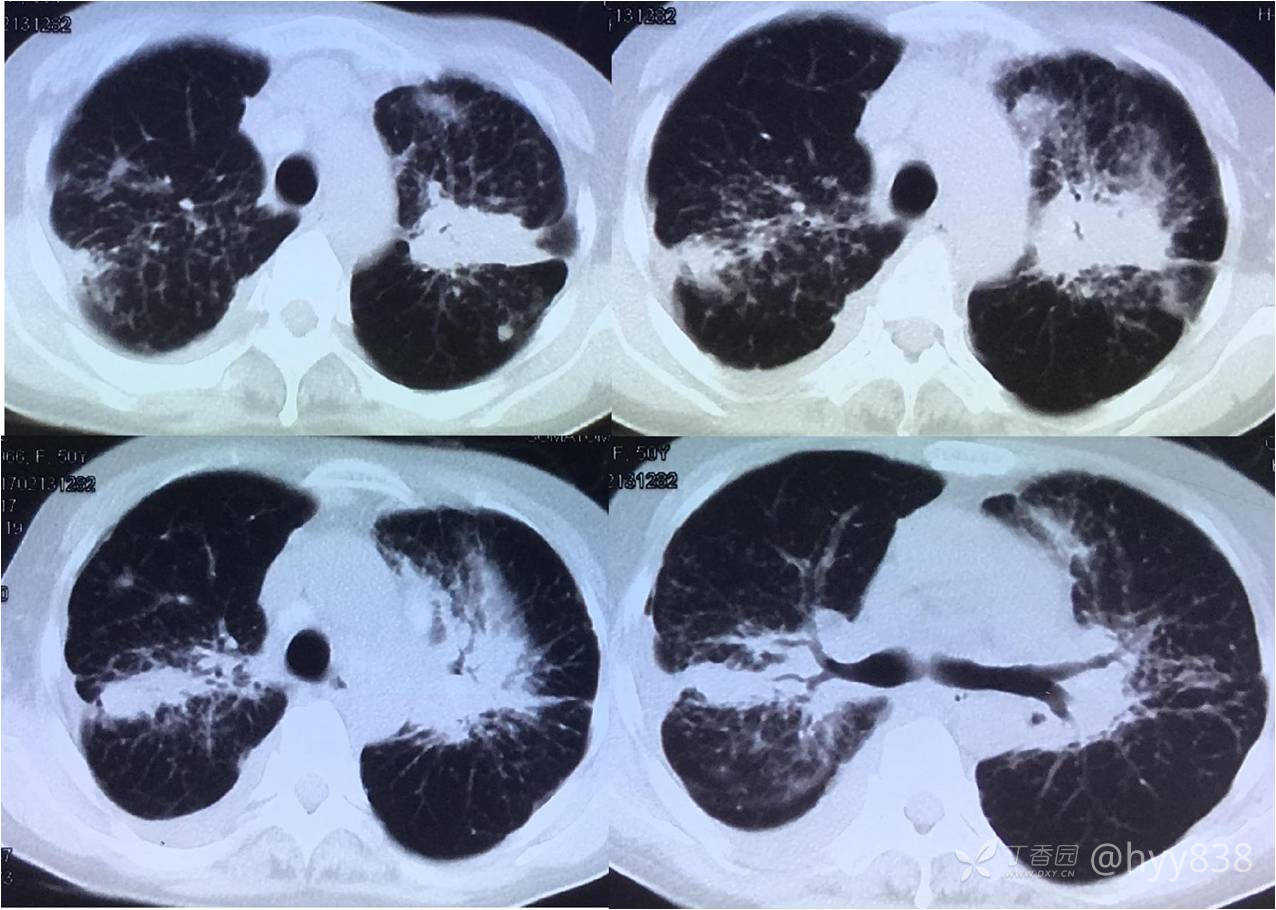

第一次胸部CT